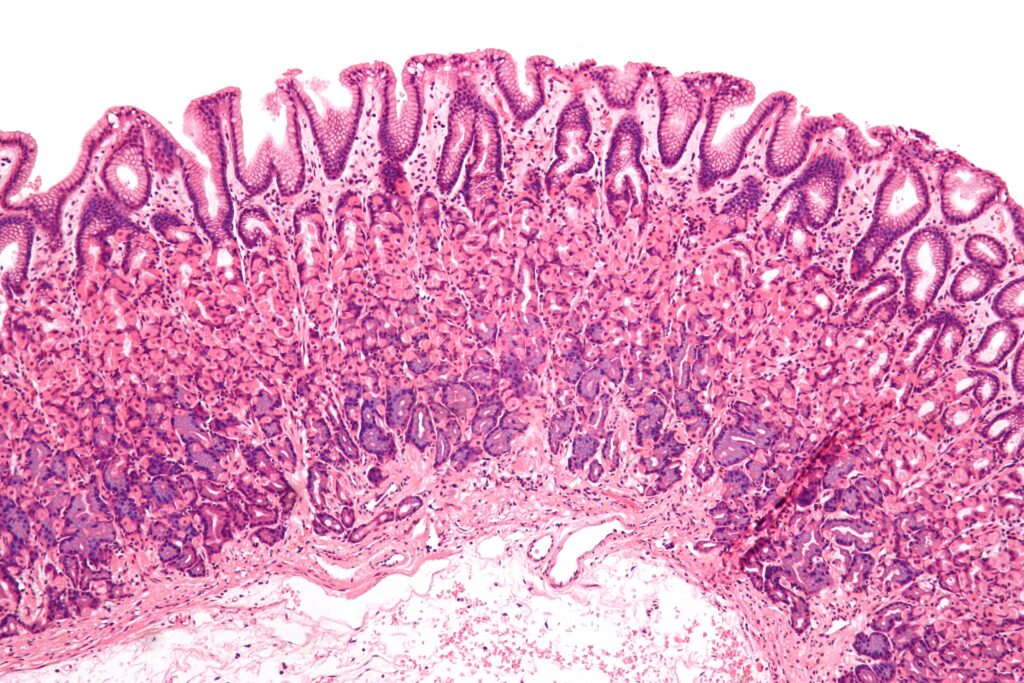

The mucous membrane lines areas of the body and covers all internal organs, it is a natural part of our bodies and is made up of “one or more layers of epithelial cells overlying a layer of loose connective tissue”.

Gastric Mucosa (Gastric Mucous Membrane)

In addition, the mucous membrane protects the body in numerous ways, including from itself. For example, “the stomach is protected from stomach acid just as the bladder’s underlying tissue is protected from urine”.